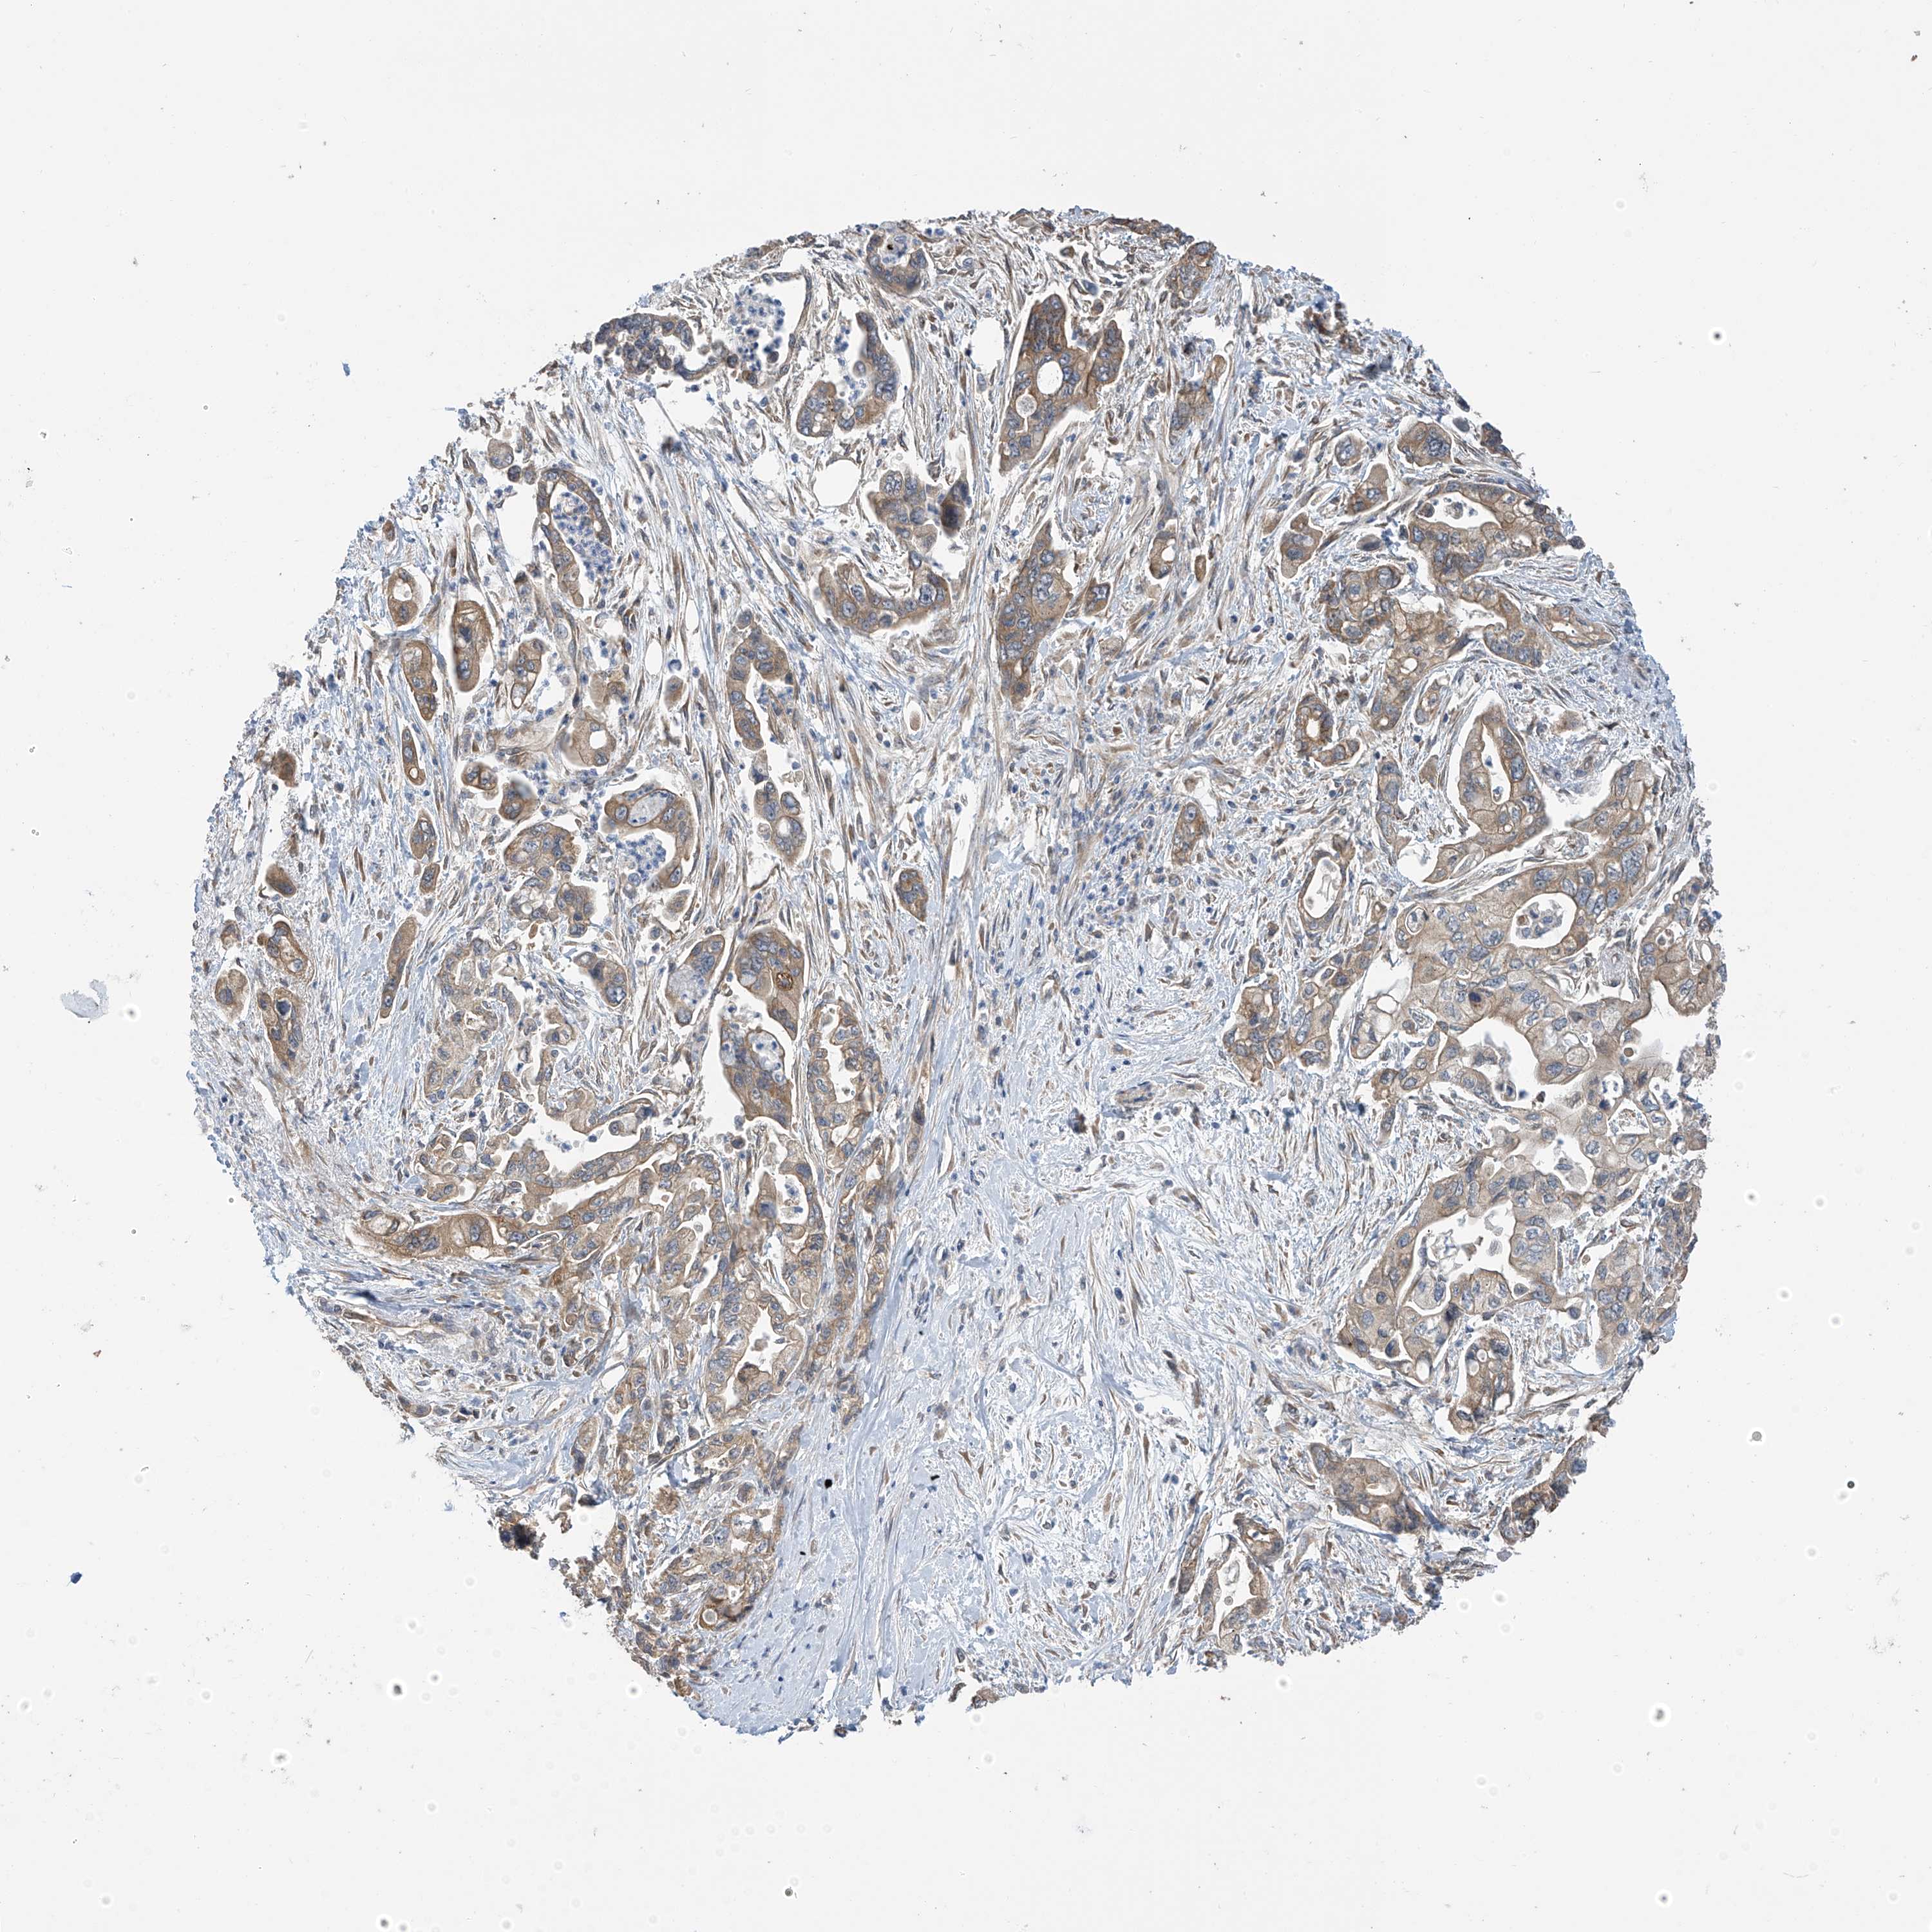

PANCREATIC CANCER - Protein expressioni

A mouse-over function shows sample information and annotation data. Click on an image to view it in a full screen mode. Samples can be filtered based on level of antibody staining by selecting one or several of the following categories: high, medium, low and not detected. The assay and annotation is described here.

Note that samples used for immunohistochemistry by the Human Protein Atlas do not correspond to samples in the TCGA dataset.

Antibody stainingi

Antibody staining in the annotated cell types in the current human tissue is reported as not detected, low, medium, or high, based on conventional immunohistochemistry profiling in selected tissues. This score is based on the combination of the staining intensity and fraction of stained cells.

Each image is clickable and will lead to virtual microscopy that enables deeper exploration of all samples and also displays staining intensity scores, fraction scores and subcellular localization as well as patient and tissue information for each sample.

Antibody HPA034602

Antibody HPA034603

Antibody CAB033424

Staining

High

Medium

Low

Not detected

Intensity

Strong

Moderate

Weak

Negative

Quantity

>75%

75%-25%

<25%

None

Location

Nuclear

Cytoplasmic/membranous

Cytoplasmic/membranous,nuclear

Adenocarcinoma, NOS